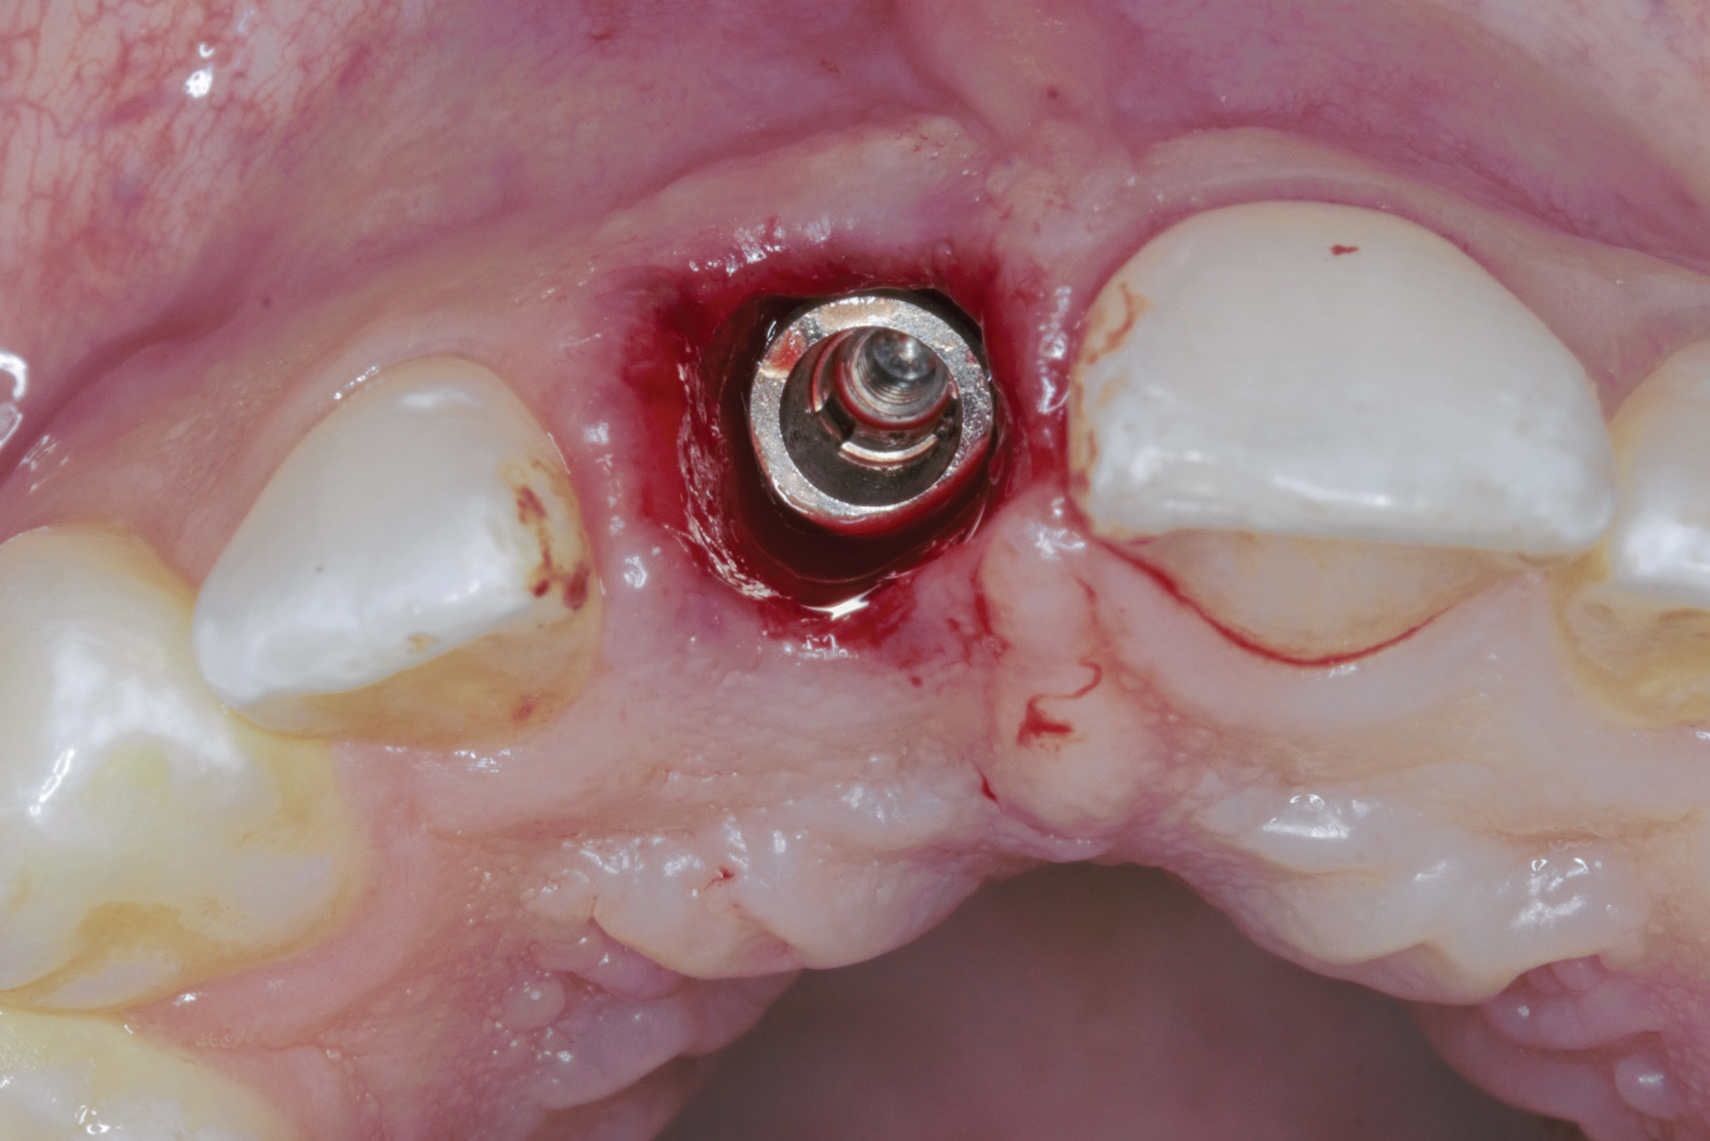

Fig 2. Immediate implant placement.

Figure 2